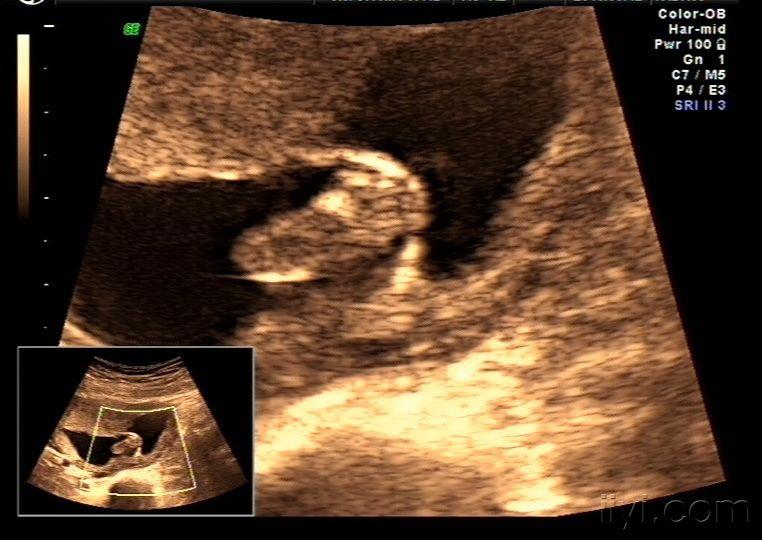

早孕:这个是羊膜囊吗? - 超声医学讨论版 - 爱爱医医学论坛

向羊膜腔内突起的囊性回声是什么?